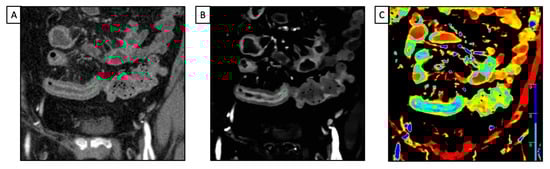

DECT has proven to have many applications, including in the evaluation of gastrointestinal tract diseases. In emergency settings, CECT is typically the preferred imaging tool when acute bowel ischemia is suspected to assess a decreased or lack of bowel parietal enhancement. However, detecting these findings is not always straightforward, especially in the case of early ischemia [42]. DECT can improve confidence in diagnosing bowel ischemia due to its capability in enabling a quantitative measure of wall enhancement via iodine mapping. In addition, a low-keV VMI can highlight the attenuation differences between perfused and non-perfused walls [43,44] (Figure 3).

Figure 3.

A 49 y-o male with known Crohn’s disease, diffuse abdominal pain, and suspected relapse of disease underwent abdominal CT. (A) Conventional CT images on the coronal plane acquired after intravenous contrast media injection show a poor layered enhancement appearance of the distal ileum; (B) iodine map enhances iodine’s uptake by the mucosa layer, and the hypoattenuating appearance of the submucosa one, consistent with edema; (C) the Z-effective map allows us to define the pattern of enhancement due to the atomic number of iodine.

Among the different spectral technologies, dl-DECT is particularly useful because it allows for the simultaneous acquisition of low- and high-KeV information at the same spatial position, facilitating the visualization of the un-enhanced bowel, and because the spectral dataset is always retrospectively available for every scan [45].